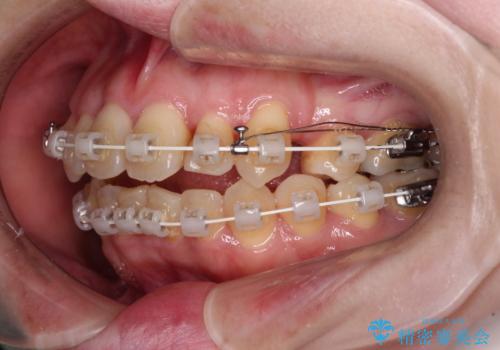

- 矯正装置

- 審美装置

舌の突出癖が強く、治療途中で上下前歯が乖離した開咬となってしまいました。

舌のトレーニングで開咬は改善できますが、なかなかトレーニングが進まず、治療期間は想定よりも長期化してしまいました。